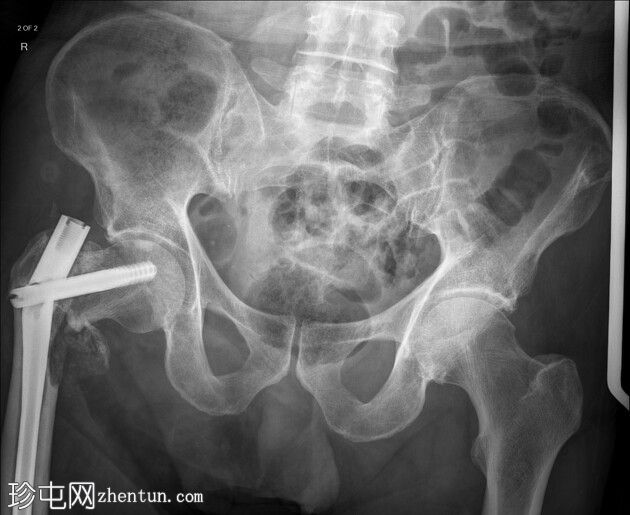

3.jpeg

侧面

跌倒后右髋关节缩短且外旋。

右侧髓内钉近端骨折(位于拉力螺钉孔位)。

空心髋螺钉组件完好。

股骨转子间骨折延伸至股骨近端转移灶,小转子粉碎。

这是股骨髓内钉断裂的典型案例。由于担心股骨近端溶骨性病变以及患者存在病理性骨折的风险,因此置入了髓内钉。髓内钉断裂是一种罕见但严重的并发症。

在本例中,髓内钉断裂发生在拉力螺钉孔(穿过股骨颈的螺钉)的水平,该水平可能是髓内钉本身较薄弱的部位。靠近该水平的溶骨性病变可能导致了不稳定性和髓内钉的异常应力。